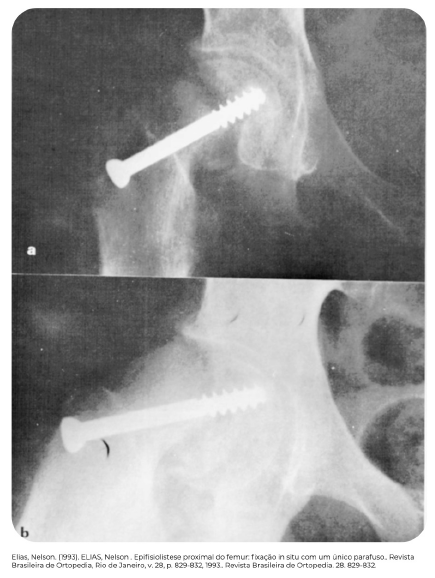

Tratamento com parafuso percutâneo

A

Pinagem percutânea

· Se epifisiólise estável

· Parafuso único entrando perpendicular à fise, em direção ao centro da cabeça femoral e 4 roscas cruzando a fise

· Evitar penetração articular

. Evitar quadrante anterossuperior - risco de NAV